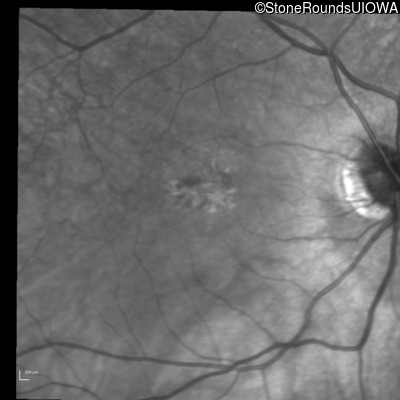

Infrared Fundus Photograph - Right - 20/100

Exemplar